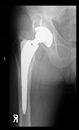

The radiological examination allowed us to verify the close bone-to-implant contact and the unchanged position of the implant during follow-up.

3. Results

In all the cases operated with the above-described targeting procedure, the stems of the cups remained between the cortical bone surfaces without perforation of the linea terminalis, as shown by postoperative radiographs. There were no complicated surgical situations. In 16 cases, the wound healings were uneventful, and the hips were able to bear weight again after postoperative rehabilitation.

The only patient who suffered an infection healed after the removal of the implant. This complication rate is known and in line with accepted values.

One septic complication occurred. This complication rate is consistent with other revision techniques. In this case, the implant had to be removed, and the patient remained in Girdlestone condition. In such cases, removal of the implants and, of course, surgical debridement and antibiotic treatment are essential. The condition after resection is called Girdlestone’s condition. We had no other complications or unexpected outcomes.